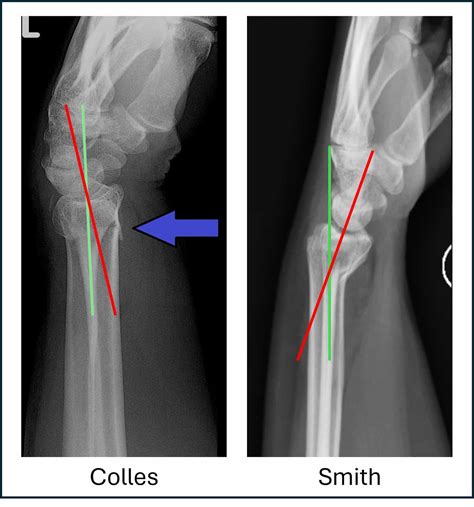

Comparing Colles Vs Smith Fracture

While both Colles and Smith fractures involve the distal radius, they have distinct characteristics that set them apart. Here is a comparison of the two:

Feature Colles Fracture Smith Fracture

Location Dorsal (back) aspect of the distal radius Volar (palm) aspect of the distal radius

Cause Fall onto an outstretched hand Fall onto the back of the hand or direct blow

Appearance "Dinner fork" deformity "Garden spade" deformity

Treatment Often non-surgical, but may require surgery for severe cases Often requires surgical intervention